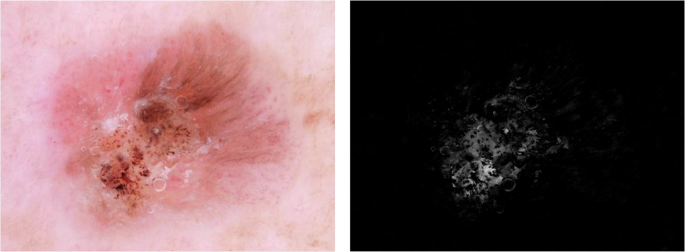

Preprocessing for vascular architecture enhancement

To enhance vessel visibility, we focused on the green channel since vascular features exhibit higher contrast in this spectrum33,34. Using OpenCV, we extracted the green channel from the original RGB image and computed its inverted complement to increase the contrast of vascular structures relative to the surrounding tissue. We then applied Contrast Limited Adaptive Histogram Equalization (CLAHE) with a clip limit of 2.0 and an 8 × 8 tile grid, parameters that were iteratively optimized to enhance local contrast and improve vessel delineation. This combination of channel inversion and adaptive contrast enhancement selectively amplified vascular patterns while reducing background noise35 (Fig. 4). The resulting preprocessed image was integrated as an additional channel into the network’s input tensor, complementing the raw RGB data and providing the CNN with enriched information on vascular architecture.